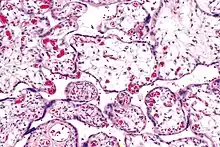

| Micrograph of villous immaturity. H&E stain. | |

Placental villous immaturity is chorionic villous development that is inappropriate for the gestational age.

Immature chorionic villi are larger and have more central blood vessels; thus, the diffusion distance for gas and nutrient exchange is larger and, therefore, placental function is impaired.

Low mag.

Low mag. High mag.